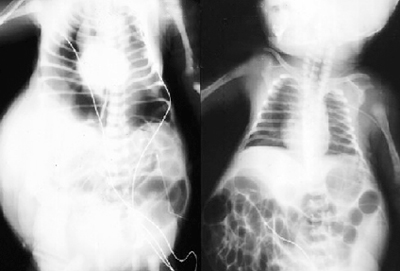

Các bậc cha mẹ cần chú ý các triệu chứng sau ở trẻ sơ sinh: trẻ không có hoặc chỉ có cơ bụng rất mỏng, khoảng da bao phủ vùng bụng đó nhăn nheo hoặc chùng xuống; ở trẻ trai, tinh hoàn bị tụt vào bên trong bụng, không thấy ở bìu; đường niệu đạo không bình thường, như: ống niệu lớn, bàng quang sưng phồng, nước tiểu tích lại hoặc chảy ngược từ bàng quang qua ống niệu lên thận; nhiễm khuẩn ống niệu do không thể bài tiết được nước tiểu. Nếu siêu âm trong thời kỳ thai nghén có thể thấy sự phát triển bất thường của bàng quang và đường tiết niệu của thai nhi. Trong khi thai nhi phát triển, dịch tiết ra trong bụng ngày càng lan rộng nhiều hơn. Nhưng chất lỏng được tái hấp thu trước khi sinh, cho nên khi sinh ra, bụng của đứa trẻ bị võng hoặc da nhăn nheo. Sau khi sinh, siêu âm và chụp Xquang có thể xác định được các tổn thương bất thường về đường tiết niệu. Dấu hiệu dễ nhận thấy nhất của bệnh là bụng trẻ sơ sinh to bất thường, da vùng bụng nhăn nheo. Trẻ sơ sinh thường xuyên bị viêm đường tiết niệu. Xét nghiệm máu, nước tiểu kiểm tra chức năng thận thấy các triệu chứng viêm nhiễm và suy thận.

Hội chứng mất cơ bụng có tên khoa học là hội chứng Prune-Belly, là khiếm khuyết bẩm sinh, trung bình ở Mỹ, cứ 40.000 trẻ có 1 trẻ mắc phải. Bệnh thường gặp ở các bé trai với tỷ lệ 96%. Hội chứng này do một rối loạn hệ thống tiết niệu bẩm sinh, có triệu chứng đặc trưng là da bụng nhăn giống quả mận khô. Bệnh có thể gây ra những hậu quả rất nghiêm trọng: 20% trẻ tử vong trước khi sinh, 30% tử vong do các bệnh về thận trong vòng 2 năm sau sinh, 50% còn lại sẽ gặp phải những bệnh về tiết niệu ở các mức độ khác nhau. |